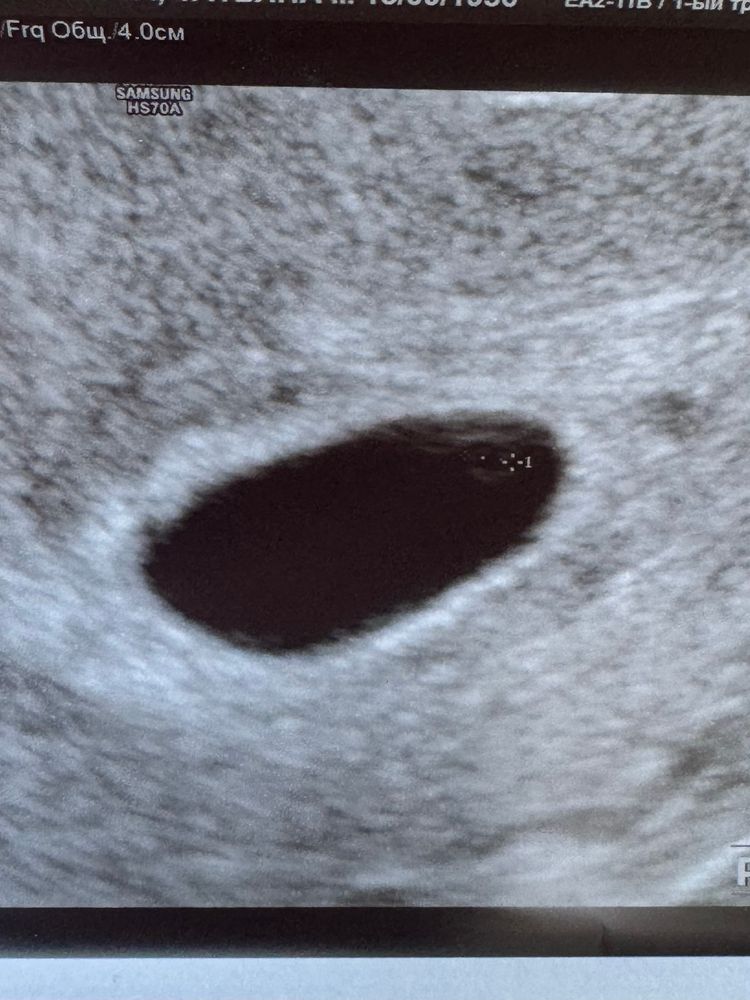

квитка, добрый день, может и у меня на снимке вы что нибудь разглядите ?)) 26дпп Изображение Изображение

Вероника, я вижу желточный мешочек и эмбрион, а врач узи что ваш увидел?)

квитка, вот эта линия похожа на эмбриошу Изображение

квитка, пока что только ЖМ 1,7мм и все, сказала замершая 😭 тк нет эмбриона. Плоднле яйцо 11,4мм. В четверг пойду к своей ре